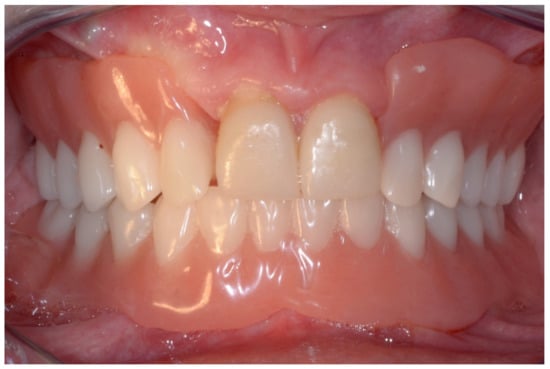

6.2.5. Postoperative (2-Years Follow-Up) Documentation:

A screw-retained provisional fixed prosthesis was used for 4 months to condition peri-implant mucosa, and in October 2013, the final prosthesis was installed. The occlusion was adjusted, and the patient received instruction for oral hygiene. A follow-up assessment at 8 years showed a stable cosmetic, biological and functional reconstruction (Figure 27, Figure 28 and Figure 29).

Figure 27.

Resting frontal close-up views.

Figure 28.

Smile frontal close-up views.